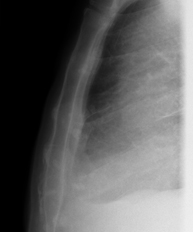

- Chest X-ray

A chest X-ray uses a small dose of radiation to obtain a two-dimensional image of the thoracic cavity and its contents (lungs, heart, mediastinum, etc.). It is one of the most commonly performed medical tests.

- Tórax

- RX Tórax

Técnica mediante la cual, utilizando rayos X, se obtienen imágenes de la caja torácica (corazón, pulmones, arcos costales, clavículas, etc.) para su estudio. - RX Esternón